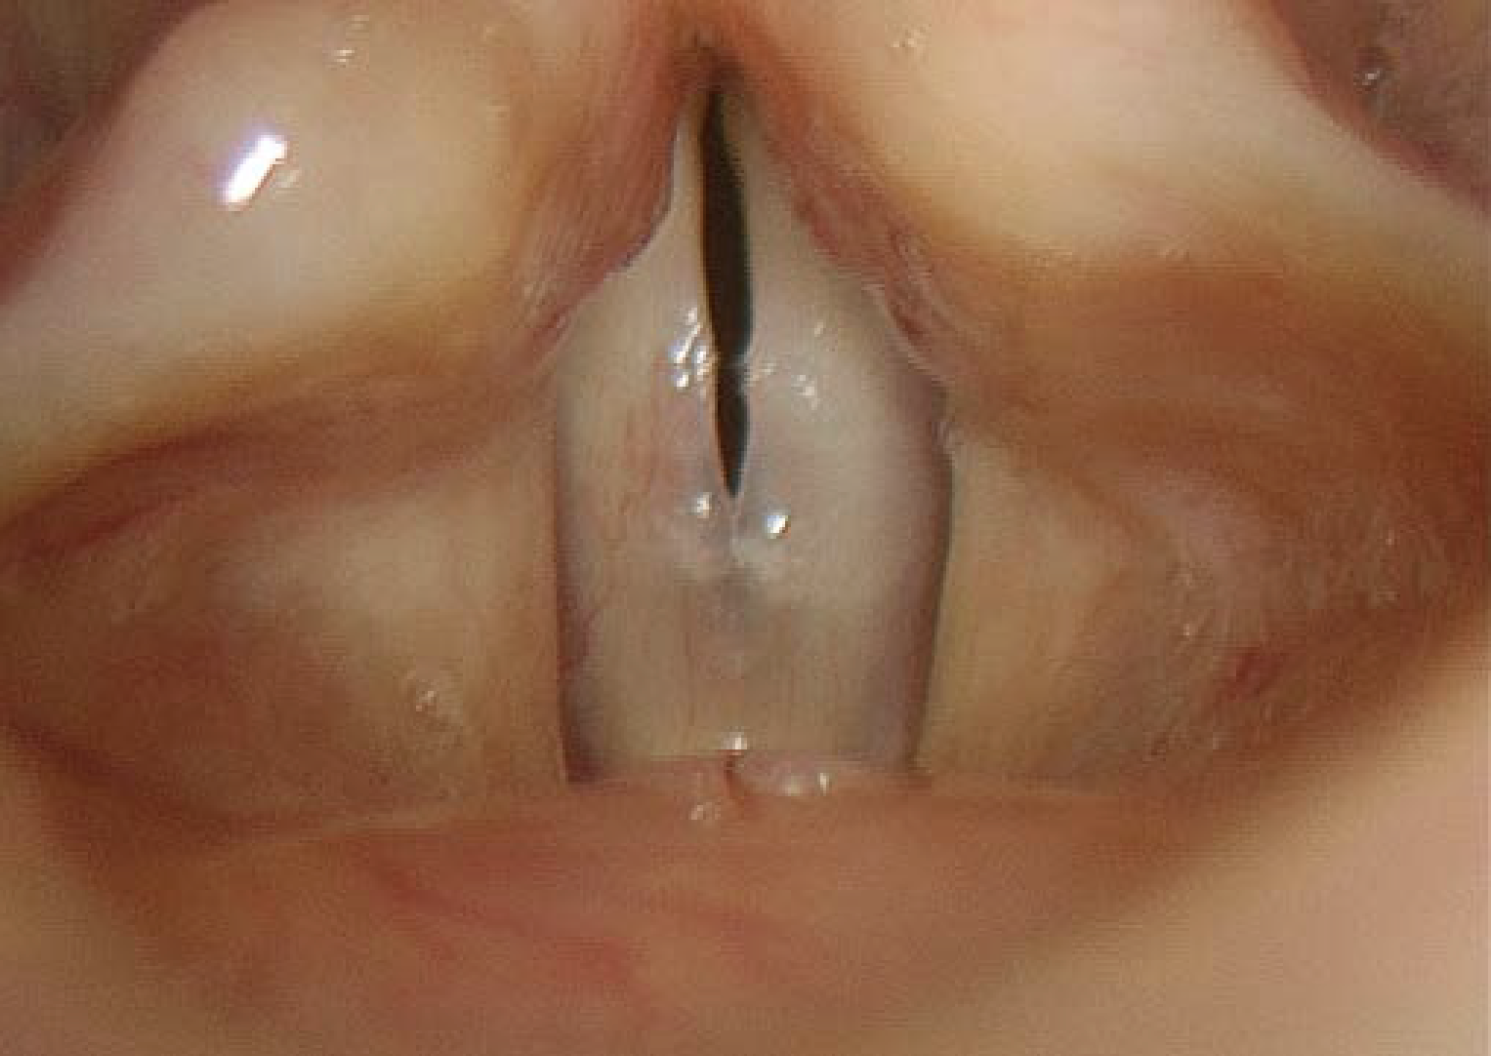

→ Glottic Closure (vocal fold closure)

– Complete / incomplete

→ Open Quotient

→ Glottal Gap

– Posterior / anterior / elliptical / hourglass

→ Mucosal Wave

– Symmetrical / asymmetrical

– Normal / diminished / extended

– Absent